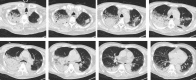

Case presentation: The patient had a history of hypertension, laryngeal cancer, chronic obstructive pulmonary disease, and type 2 diabetes mellitus. Following a cerebral arteriovenous malformation hemorrhage, he underwent surgery to remove the hematoma and began rehabilitation. On day 66 of hospitalization, he suddenly developed a fever, and coarse crackles and wheezes were heard in his right lung. A diagnosis of hospital-acquired aspiration pneumonia was made, and initial treatment with piperacillin/tazobactam was started. Teicoplanin was added after S. pneumoniae was isolated from the blood culture, however, the patient died 5 days later. The S. pneumoniae detected in the sputum smear was serotype 3, showed mucoid colonies and susceptibility to penicillins, cephalosporins, carbapenems, and levofloxacin, but resistance to erythromycin.

Conclusion: We experienced a fatal case of pneumonia caused by mucoid serotype 3 S. pneumoniae with a thick capsule. Serotype 3-associated pneumonia may develop a wider pulmonary infiltrative shadow, a prolonged therapeutic or hospitalization course, and a poor outcome. Careful observation and intervention are required, and the use of additional antibiotics or intravenous immunoglobulins should be considered in such cases. Pneumococcal immunization is also an important public health measure to minimize the development of severe infections caused by serotype 3 strains.